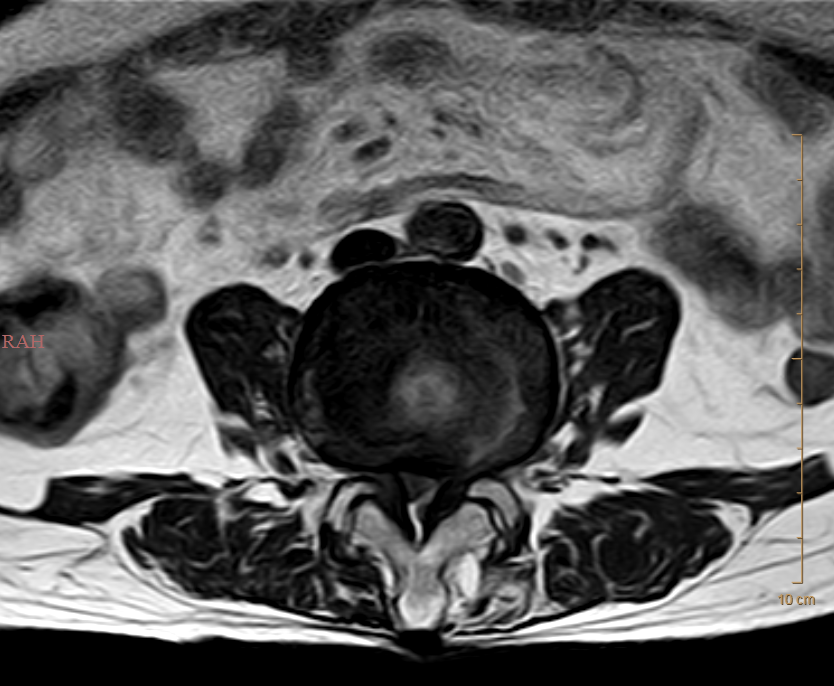

术前

胡奶奶虽然高龄,但身体尚健,被腰椎间盘突出症折磨了二十余年,近期疼痛加剧伴行走困难。经我院骨一科团队详细评估,为其采用了经皮射频热凝联合胶原酶化学溶解术。该微创方案无需开刀,仅通过穿刺针操作,利用射频热凝精准阻断疼痛信号,同时于硬膜外前间隙即盘外注入胶原酶溶解突出髓核,从根源解除神经压迫。